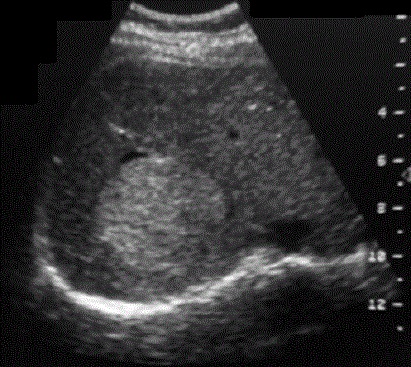

- Image echographique

de kyste simple du foie est :

Aspect lesionel anechogene , homogene ,arrondie ou ovalaire a

renforcement echoriche posterieur . Sa contour est. net , lisse

, peut etre en cloisone et avascularisation

Aspect lesionnel du kyste est arrondie aechogene a

bord tres nette et lisse , situe

a lobe droit du foie . Ombre de hyperascoustique porterieure

du kyste en visualise tres net . Image echographie

percutanee du kyste simple du foie |